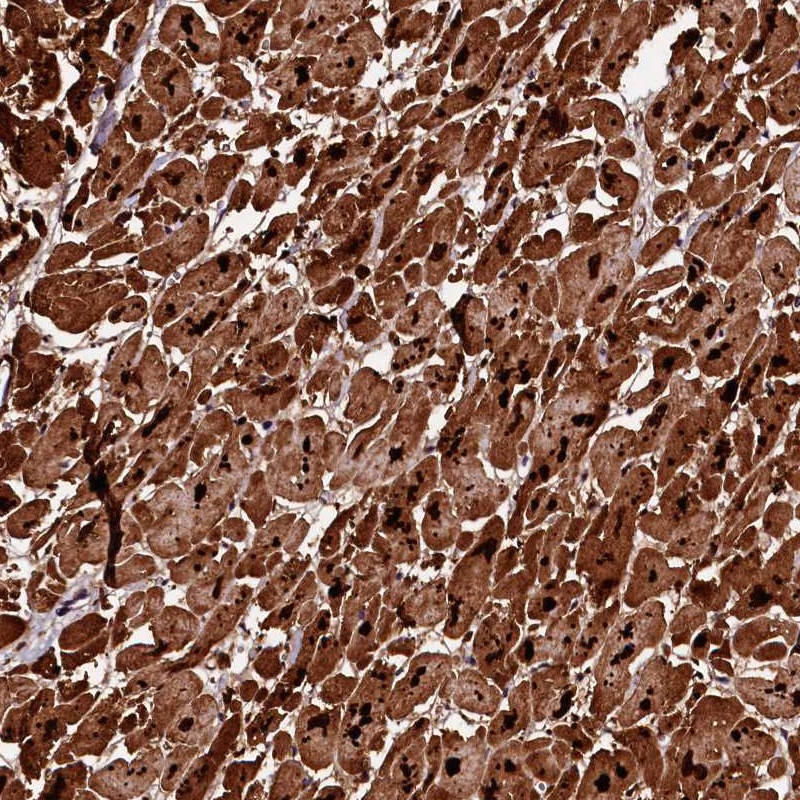

Immunohistochemical staining of human heart muscle shows strong cytoplasmic positivity in myocytes.